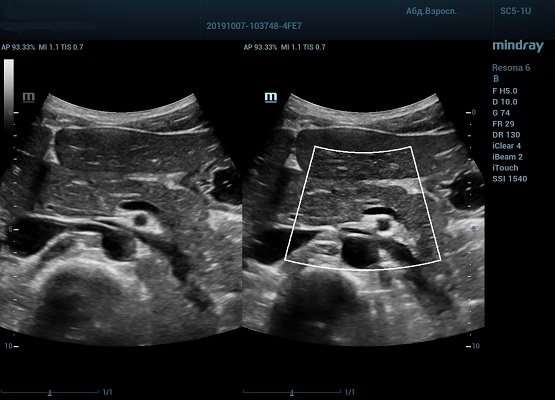

HD Scope позволяет достигать поразительной разрешающей способности выбранной зоны сканирования, при этом улучшая как детализацию, так и контрастность изображения. Помимо пространственного разрешения мы получаем преимущество и по разрешению во времени. Прибор получает огромное количество нативных изображений практически одновременно, и при сборе итоговой картины не происходит смещения объекта под датчиком, а значит и нет размывания изображения. Все участки раздела фаз, каждый контур образования теперь видны, мы все ближе к идеальной картинке.

Как он работает? Особенностью платформы ZST+, на которой построены приборы Mindray Resona, является так называемое многолучевое сканирование. В отличие от обычного датчика, который получает изображение в виде прямого эхо, датчики приборов этой серии проводят многолучевое сканирование каждым элементом с огромной скоростью, получая огромное количество данных. Затем происходит сложная постобработка и сбор из множества «многолучевых» снимков идеальной картинки.

Вторая особенность ультразвуковых машин данной линейки — это изменение расчетных констант распространения ультразвука, таким образом прибор перебирает для каждой ткани свои значения скоростей волны и пересчитывает каждую точку, делая менее выраженным поглощение по глубине. Эти особенности позволили использовать без фокусные технологии сканирования. Функция HD Scope позволяет использовать эти ресурсы для исследование небольшой области, значительно увеличивая качество изображения.